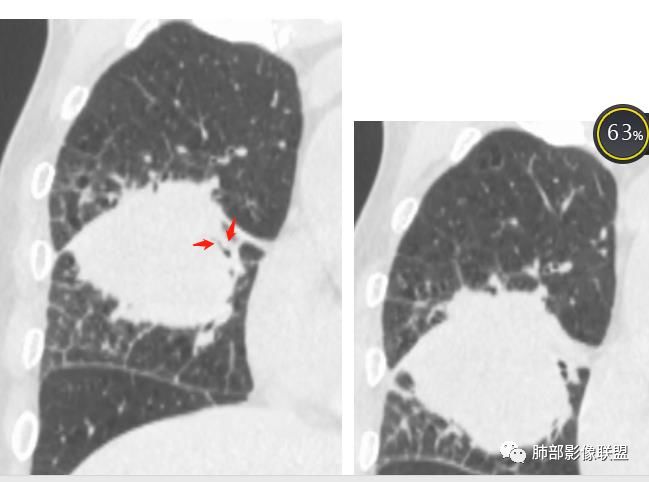

初学者:

可以看到斜裂一侧往上一侧往下,那么就是说病灶应该是起源中叶,往上,往下侵犯这样

只有这个位置起源得才能做到,将叶间裂上下往不同方向推

斜裂向下推移了,水平裂向上推移了。

下半段斜裂推移朝下

水平裂推移朝上

定在中叶应该没问题